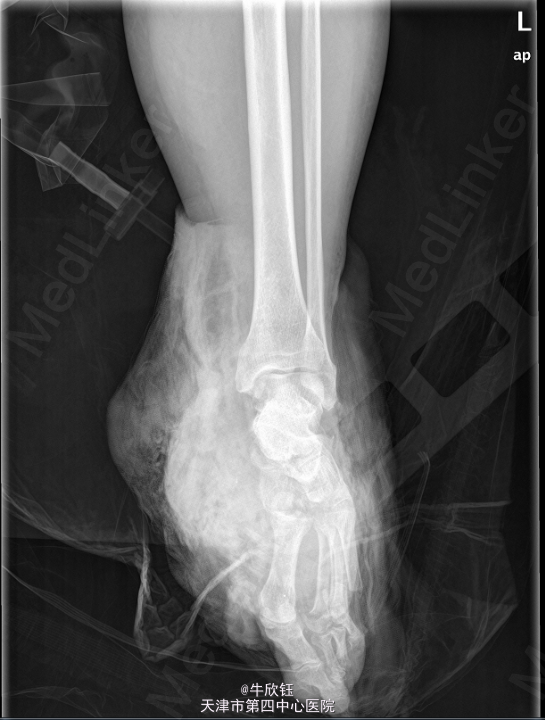

患者,女,71岁,因“外伤致左足出血疼痛伴活动受限1小时”入院。患者于1小时前意外车祸 致左足出血疼痛,血量多,疼痛呈持续性,难忍,伴活动困难,当即不能行走,无其他部位受 伤,足部大面积皮肤损毁。

左足出血肿胀明显,皮肤大面积损毁,局部散在瘀斑,左足活动受限,关节间隙压痛(+)。 我院X片:左腓骨下端骨折。左第5跖骨远端骨折,断端分离。左足诸跗骨间隙宽窄不一。左足 软组织肿胀明显。

初步诊断: 左足损毁伤 处理:全麻下行左小腿中段截肢术。

该病例左腓骨下端骨折严重,皮肤条件差。考虑保肢效果差,经讨论后家属选择截肢。